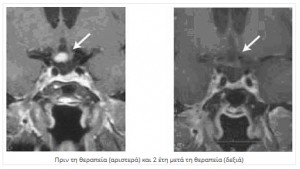

Υπάρχουν και μηνιγγιώματα που αντιμετωπίζονται αποκλειστικά με ακτινοχειρουργική λογω της θέσης τους: σηραγγώδους κόλπου, οβελιαίο κόλπου, οπτικού νεύρου και σε αυτά που αναπτύσσονται όπισθεν του αποκρίματος